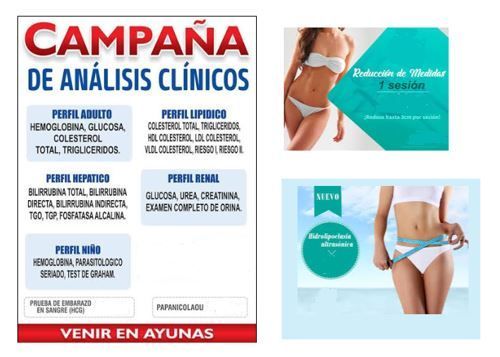

LABORATORIO CLÍNICO

- Hemoglobina, glucosa y triglicéridos.

- Colesterol total, HDL, LDL, VLDL, Riesgo I, Riesgo II.

- Bilirrubina total, directa, indirecta, TGO, TGP, fosfatasa alcalina.

- Urea, creatinina, examen completo de orina.

- Parasitológico, seriado, test de Graham

- Prueba de embarazo en sangre HCG.

YESOTERAPIA LIPOLITICA

- Reduce la cintura de 1 a 3 cm diarios.

- Sesiones de 50 min.

- Tratamiento que elimina grasa en zonas como: abdomen, muslos, glúteos, brazos y papada.